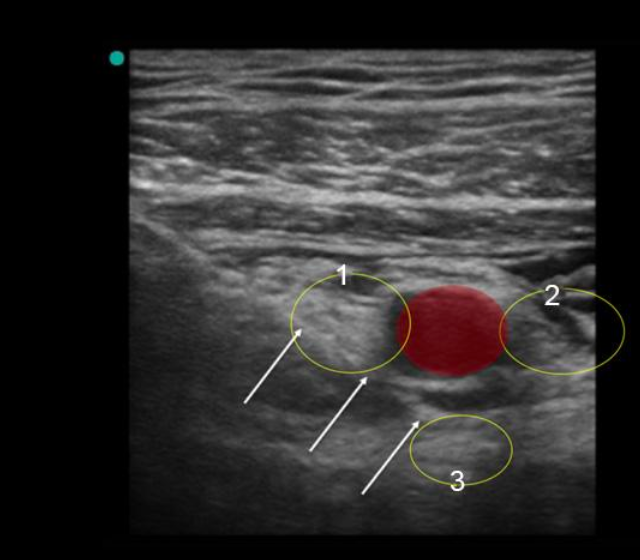

Infraclavicular Ultrasound Technique Image

1. Lateral Cord

2. Medial Cord

3. Posterior Cord

4. Needle (with arrows pointing to it)